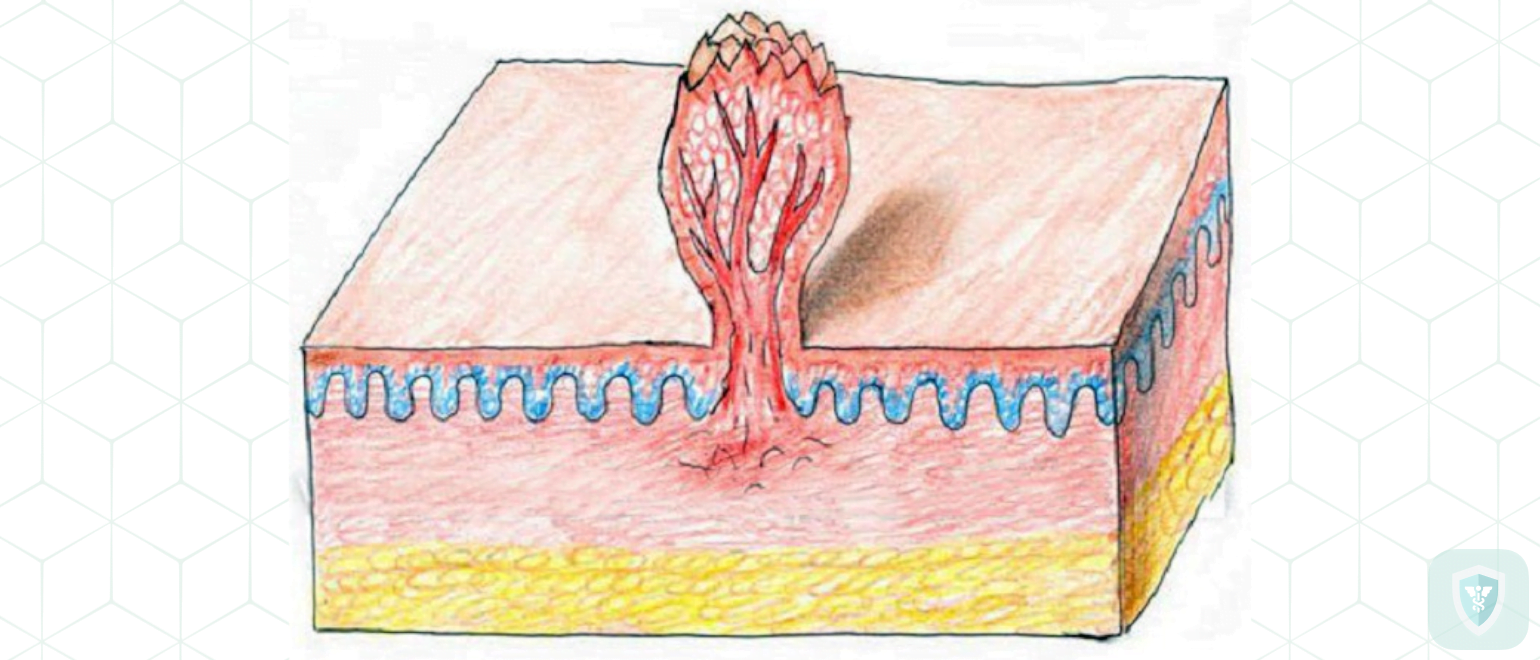

Кондиломы - это одно из самых распространенных заболеваний, передающихся половым путем. Они вызваны вирусом папилломы человека (ВПЧ) и могут появляться на внешних половых органах, анусе, ротовой полости и других областях тела.

Симптомы кондилом могут варьироваться, и визуальное представление этого заболевания может быть различным. Некоторые кондиломы выглядят как небольшие бугорки или бородавки, в то время как другие могут иметь форму плоских пятен или цветных наростов.